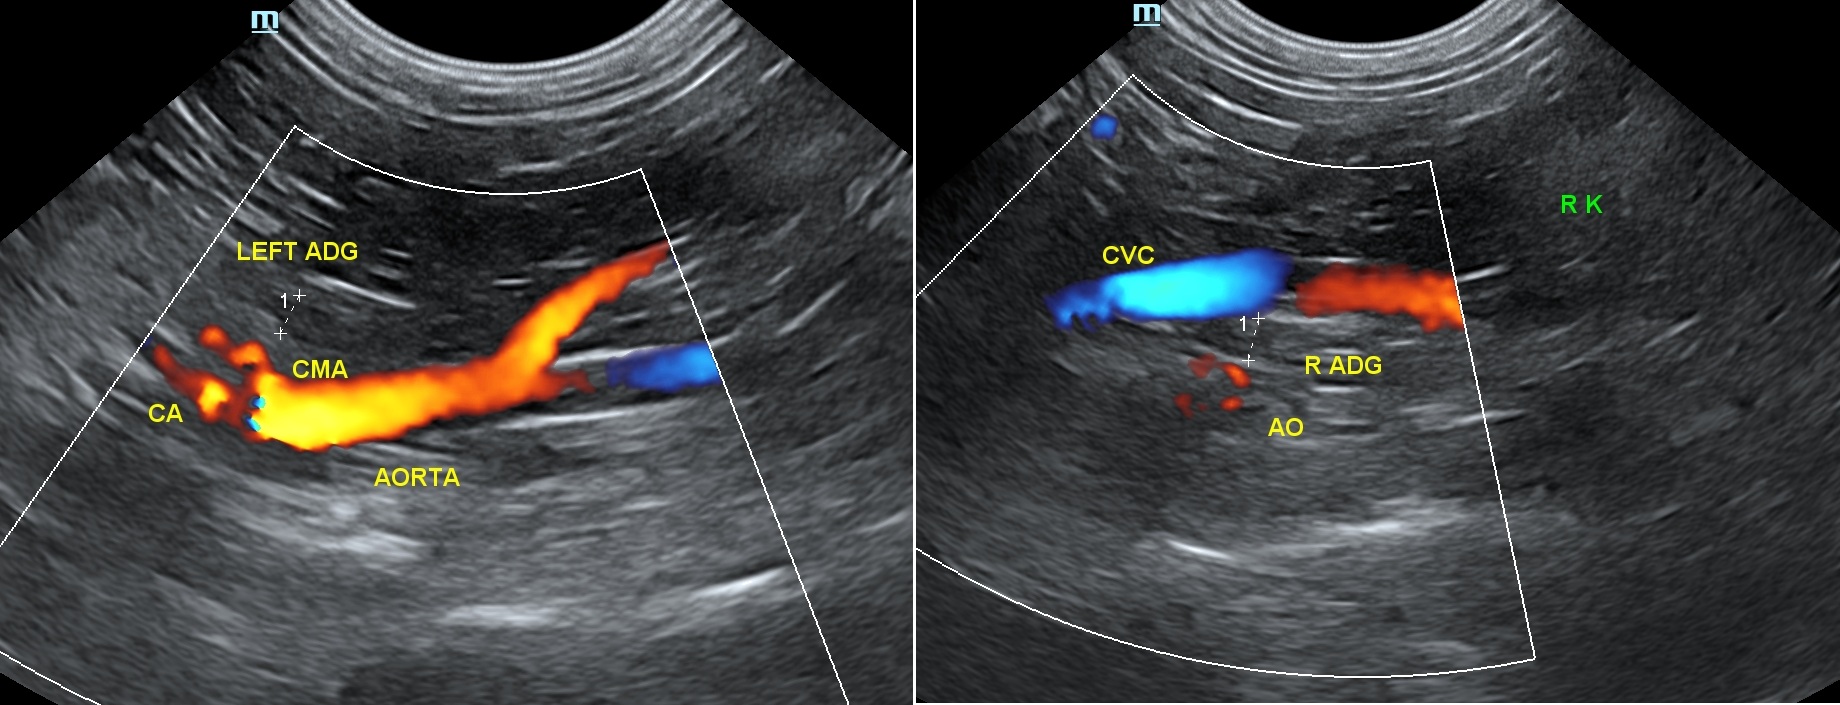

데일리벳 커뮤니티에서 좌측 부신은 환자를 dorsal recumbency나 우측 외측상으로 눕힌 뒤, 좌측 신장의 앞부분을 찾습니다. 이 지점에서 프로브를 내측으로 이동하여 시상면의 복강 대동맥을 위치한 뒤, 신장 동맥을 찾습니다. 신장 동맥을 찾은 뒤에 프로브를 동맥의 앞쪽 부분으로 약간 전진하여, 전장간막 동맥(cranial mesenteric artery)을 찾으면, 이 동맥 바로 뒤에 좌측 부신이 있습니다.

우측 데일리벳 커뮤니티을 검사하기 위해서는 환자를 dorsal recumbency나 좌측 외측상으로 눕힌 뒤, 프로브를 늑골궁 뒤에 위치시킵니다. 우측 신장의 바로 앞쪽에 있는 후대정맥(CVC; caudal vena cava)을 해부학적으로 찾는 위치(이정표)로 참고 하는데, 이는 우측 데일리벳 커뮤니티이 후대정맥의 배외측(dorsolateral)에 존재하고 있기 때문입니다. 특히 우측 데일리벳 커뮤니티을 찾기 어려운 것은 간의 바로 뒤쪽 부분의 후대정맥 근처에서 발견되고, 우측 신장의 앞내측 혹은 안쪽의 위치와 후대정맥의 등외측에서 보이기 때문입니다.(7)

데일리벳 커뮤니티에서는 좌측 부신은 대동맥에서 신장동맥보다는 전장간막동맥을 이정표로 하면 쉽게 찾으며, 우측 부신은 우측 신장의 약간 앞쪽 위치의 CVC에서 찾으면 쉽게 찾게 됩니다(7).